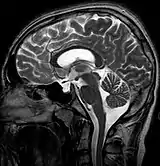

| MRI of Empty Sella | |

| Diagnostic method | MRI, CT scan[1] |

Empty sella syndrome is the condition when the pituitary gland shrinks or becomes flattened, filling the sella turcica with cerebrospinal fluid instead of the normal pituitary.[2] It can be discovered as part of the diagnostic workup of pituitary disorders, or as an incidental finding when imaging the brain.[1]